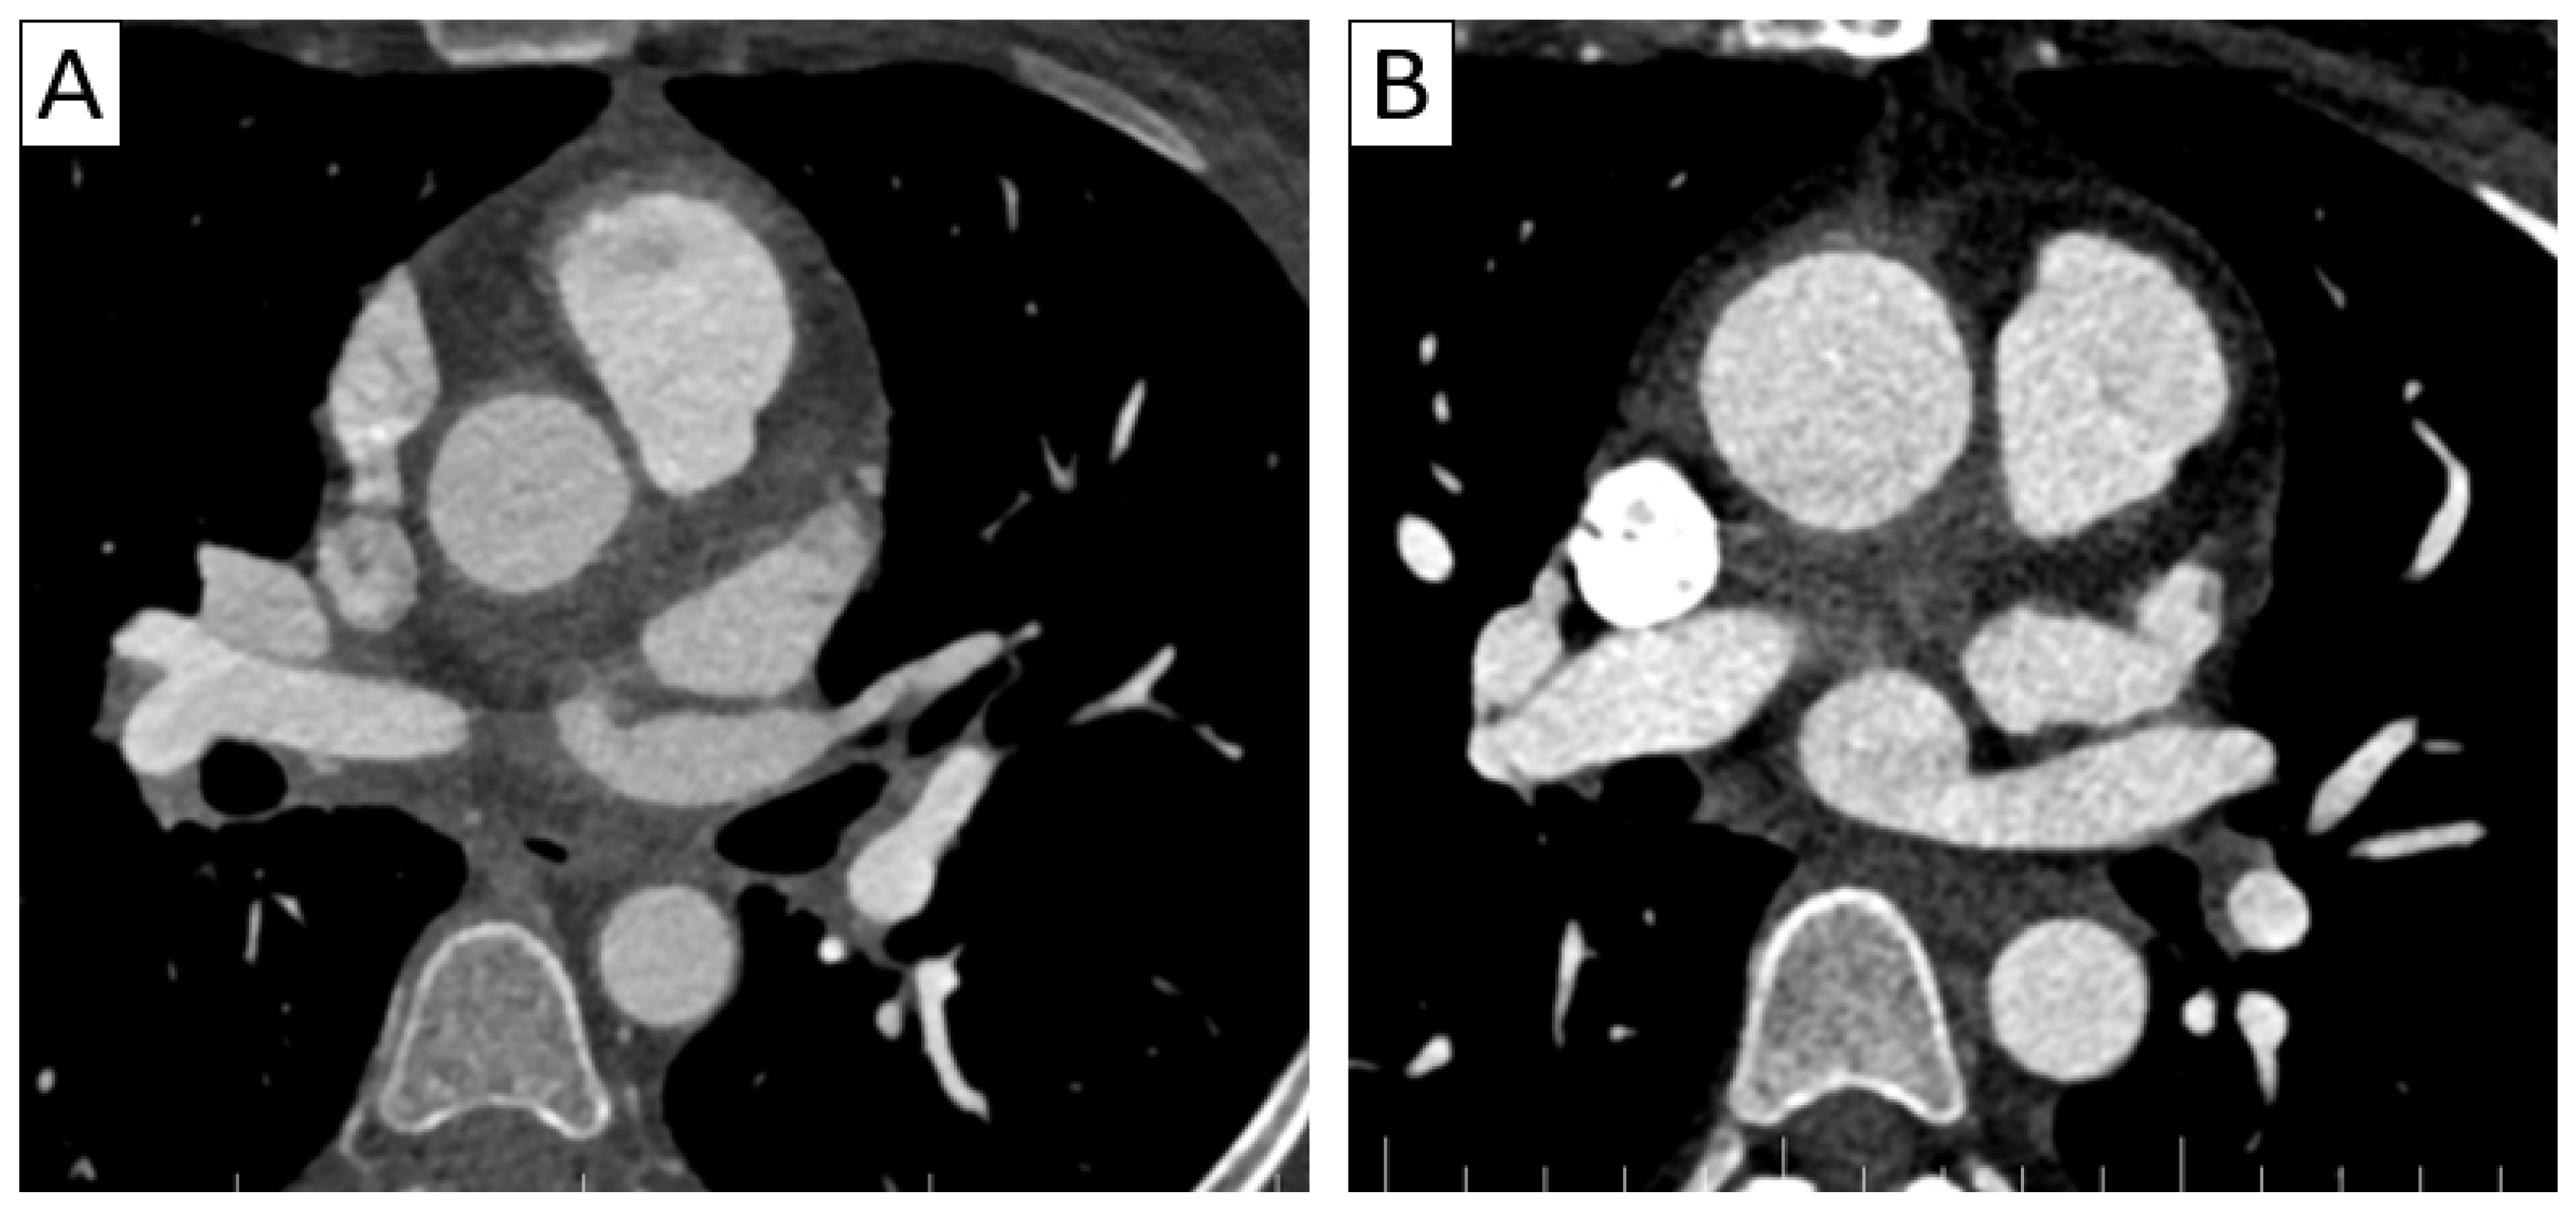

6.2.2. Takayasu Arteritis

| CTA | Circumferential parietal thickening Vessel wall enhancement | Circumferential parietal thickening Vessel wall enhancement Luminal stenosis or narrowing |